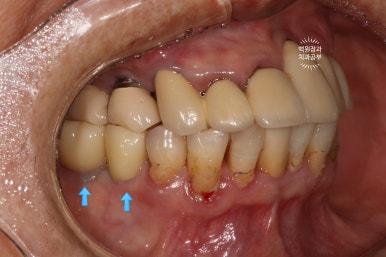

처음 오셨을 때, 치과용 파노라마 사진에서 파란색 화살표로 표시해둔 두 치아 - 왼쪽 위 송곳니와 오른쪽 아래 작은어금니가 뿌리만 남아있는 상태로 내원하셨어요.

특이할만한 점이, 두 치아 모두 신경치료와 크라운 치료를 받았던 치아였다는 것... 역시나 신경치료는 치아 건강에 그리 좋지 않음을 알 수 있습니다..

아까 말씀드렸듯, 왼쪽 위 송곳니와 오른쪽 아래 작은어금니에 뿌리만 있는 잔존치근이 관찰됩니다.

개인적으로 이를 뽑으면서 동시에 심어내는 발치 즉시 임플란트에 보수적인 의사입니다만,

이렇게 비록 치아가 썩어서 부러졌을지언정 만성치주염없이 건강한 잇몸뼈를 가지신 분은 충분히 고려해볼만 하죠!!

그래도 발치 동시에 임플란트를 심어내는 것은 여러가지 사항이 고려되어야 하고, 신중하게 접근할 필요가 있습니다.

좌측은 위턱 사진, 오른쪽은 아래턱 구강내 사진입니다.

아주 어렵지 않게 두 치아가 부러져 있다는 것을 확인할 수 있죠.